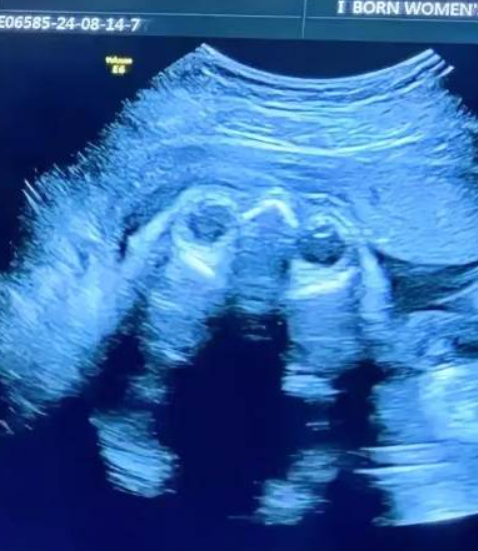

有位媽媽已經有兩個女兒,為了生個男孩拼了三胎…

到了第七個月產檢時,醫生突然留下神秘密碼「147258」,她看了半天完全不懂,當場崩潰到快哭😭

事情是這樣的:這位媽媽非常希望能有個兒子,整個懷孕過程既緊張又忐忑。產檢時,醫生神秘地在單子上寫下「147258」,說這組數字有「參考意義」。可她盯著看了好久,完全摸不著頭緒,只能自言自語:「這到底什麼意思啦?」